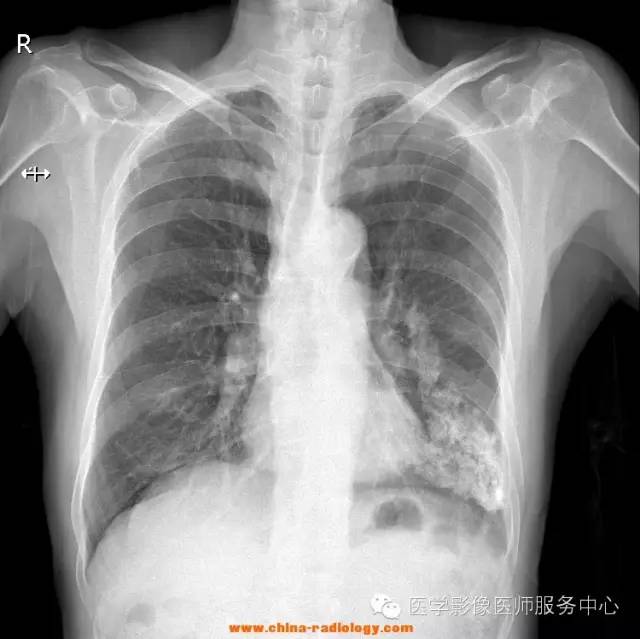

79Y,M,20160420。间断性咳嗽、胸闷多年。

透视下转位,切线位下,见侧胸壁上片状钙化影,并不随肺呼吸而运动。